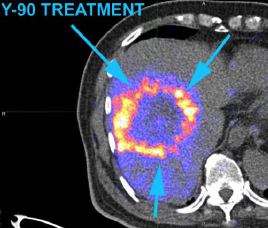

- Y-90 Liver Selective Internal Radiation Therapy (SIRT)

- Tc-99m MAA (Left) to simulate Yttrium-90 particle distribution

- Calculate Prescription Dose from dual tracer PET/CT

- Use PET/CT to scan Yttrium-90 particle distribution (Right)

Pre-treatment Tc-99m MAA SPECT/CT Post-treatment Y-90 PET/CT